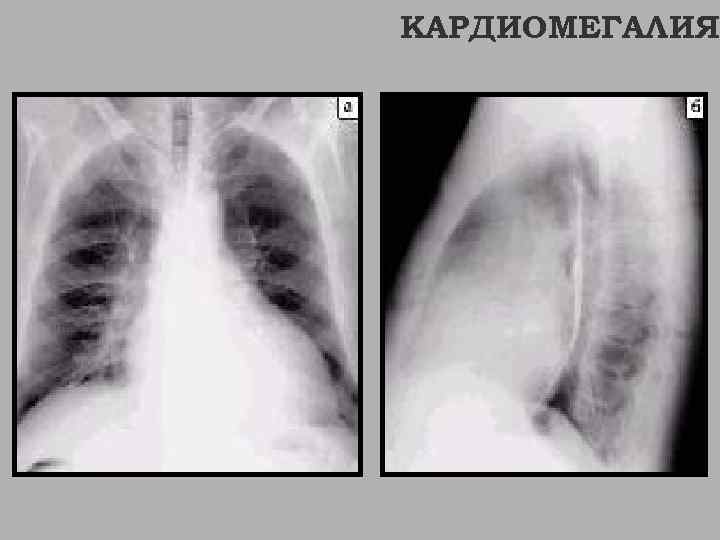

КАРДИОМЕГАЛИЯ